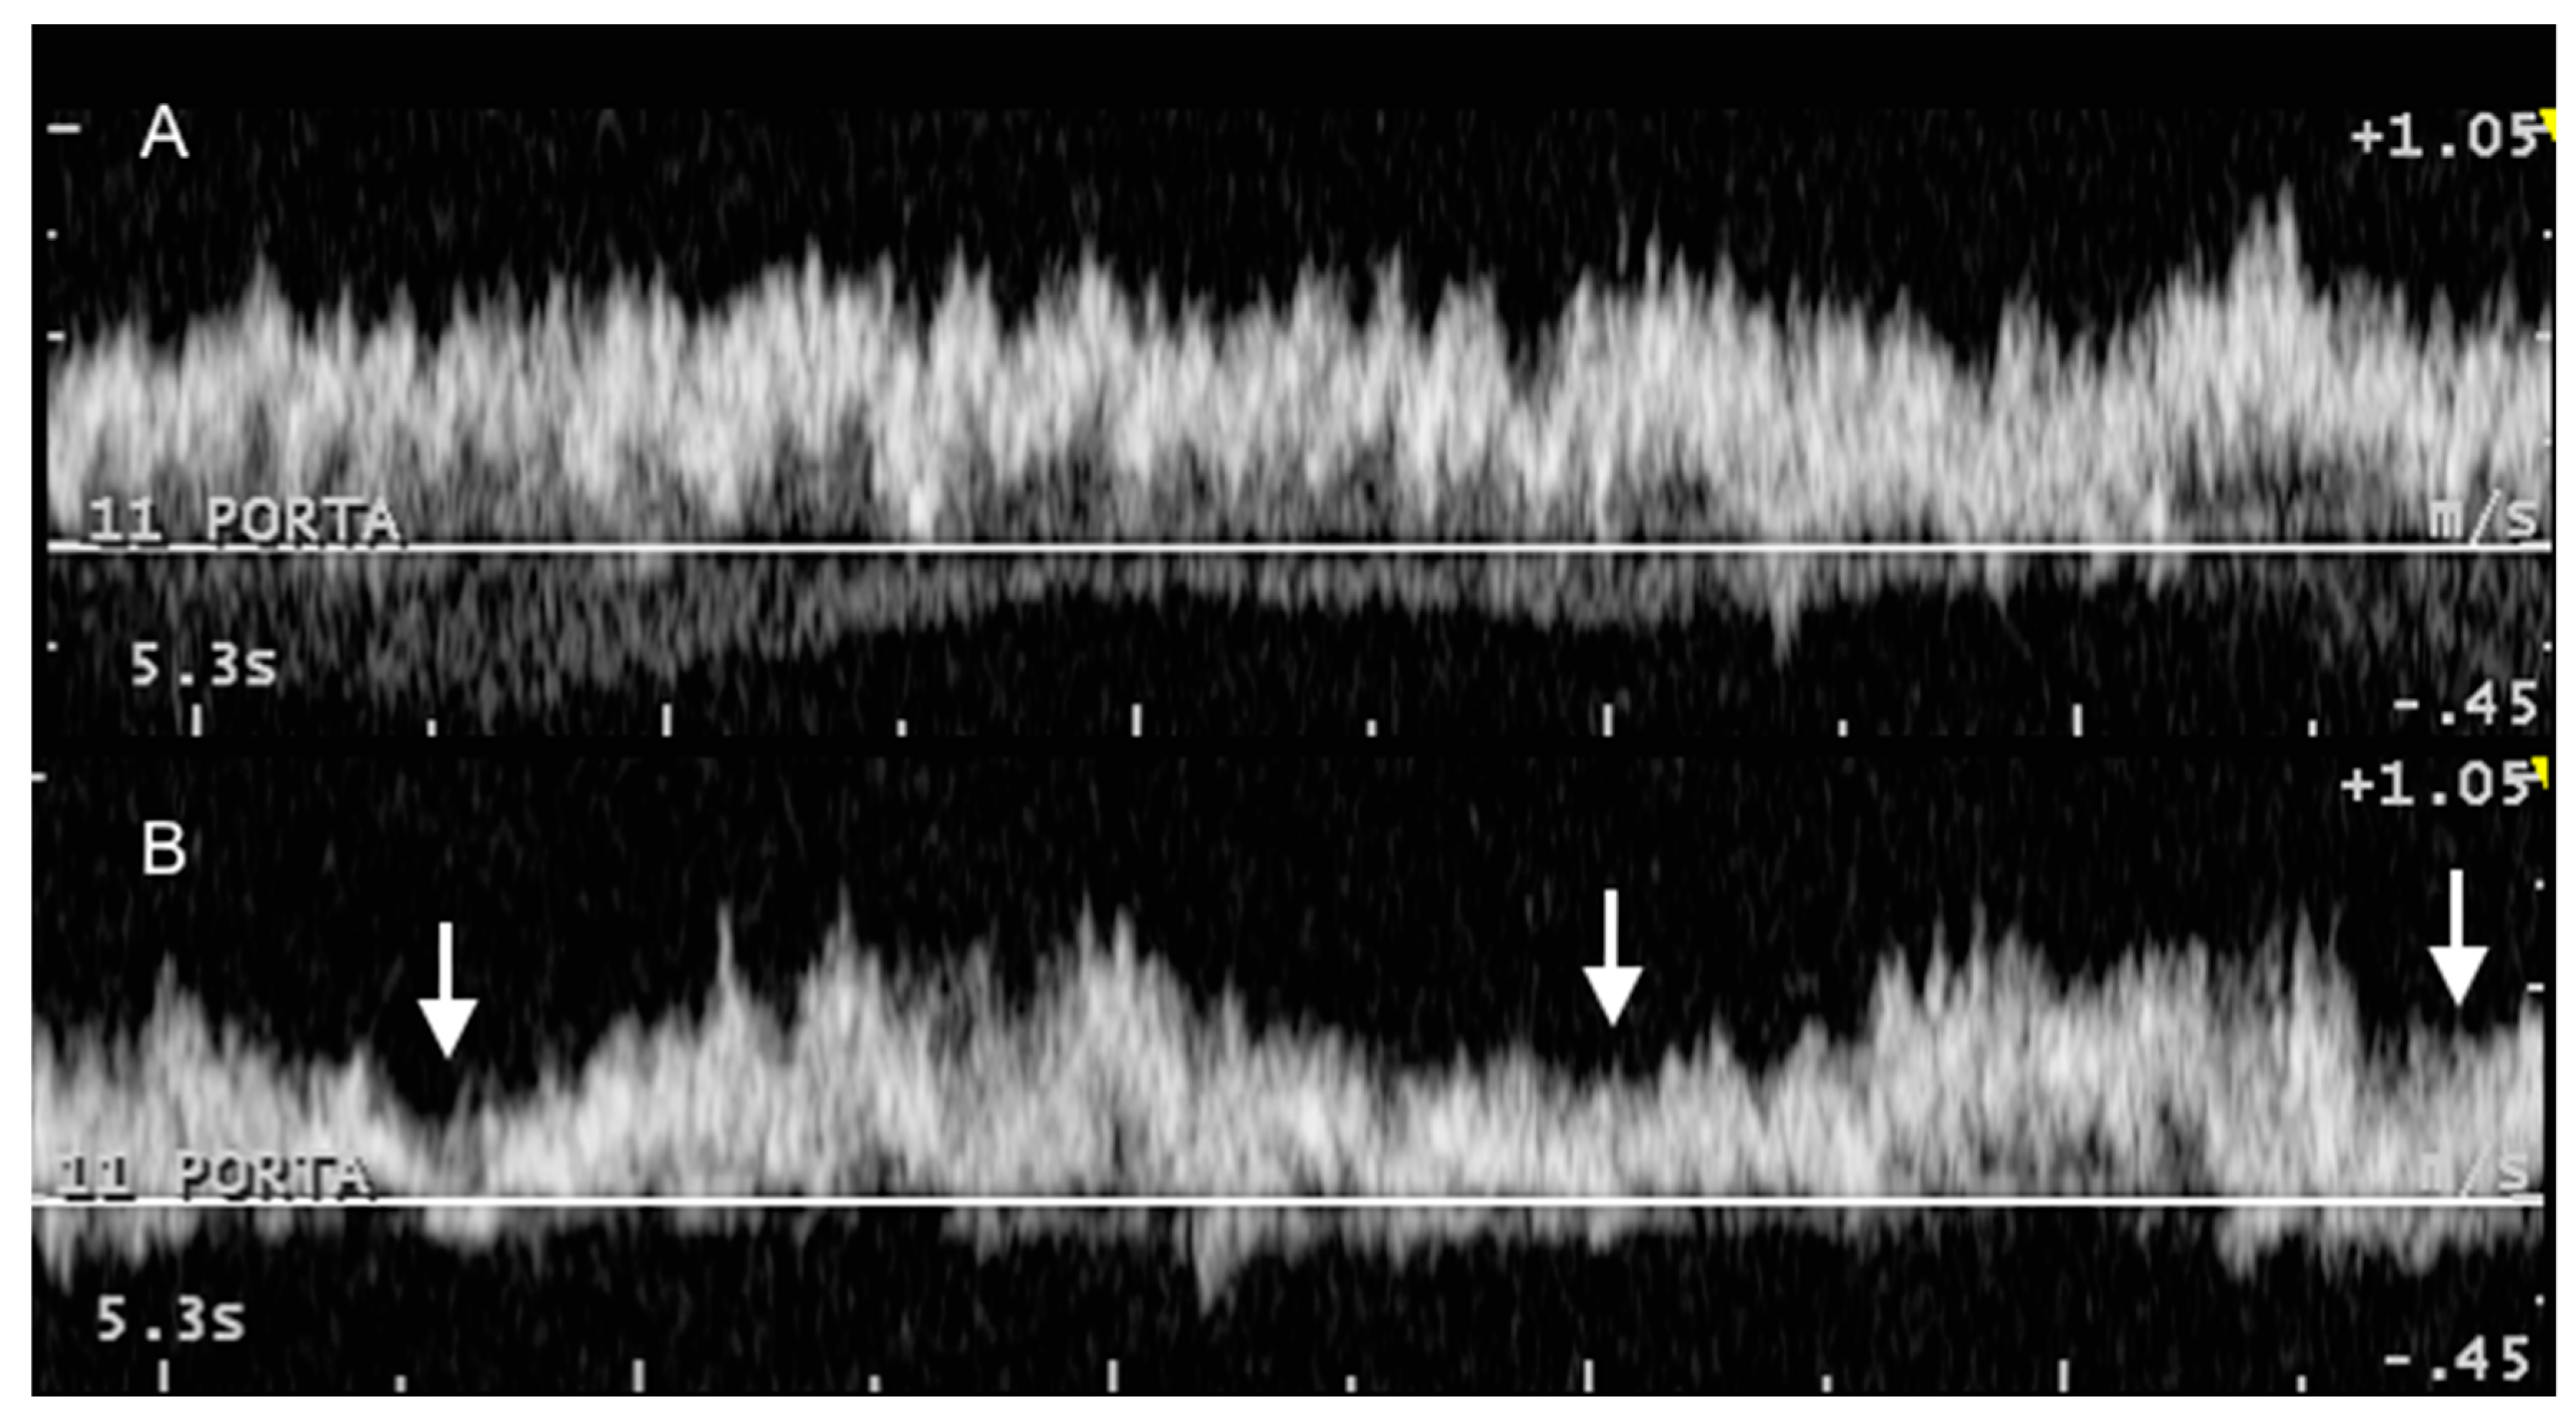

3.2. Portal System

3.3. Caudal Vena Cava and Hepatic Veins